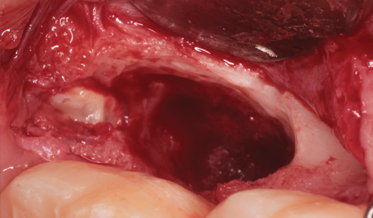

Use of Tuberosity Tissue Block for Tunneling Reconstruction of Class III Sockets With Simultaneous Implant Placement: A Case Report